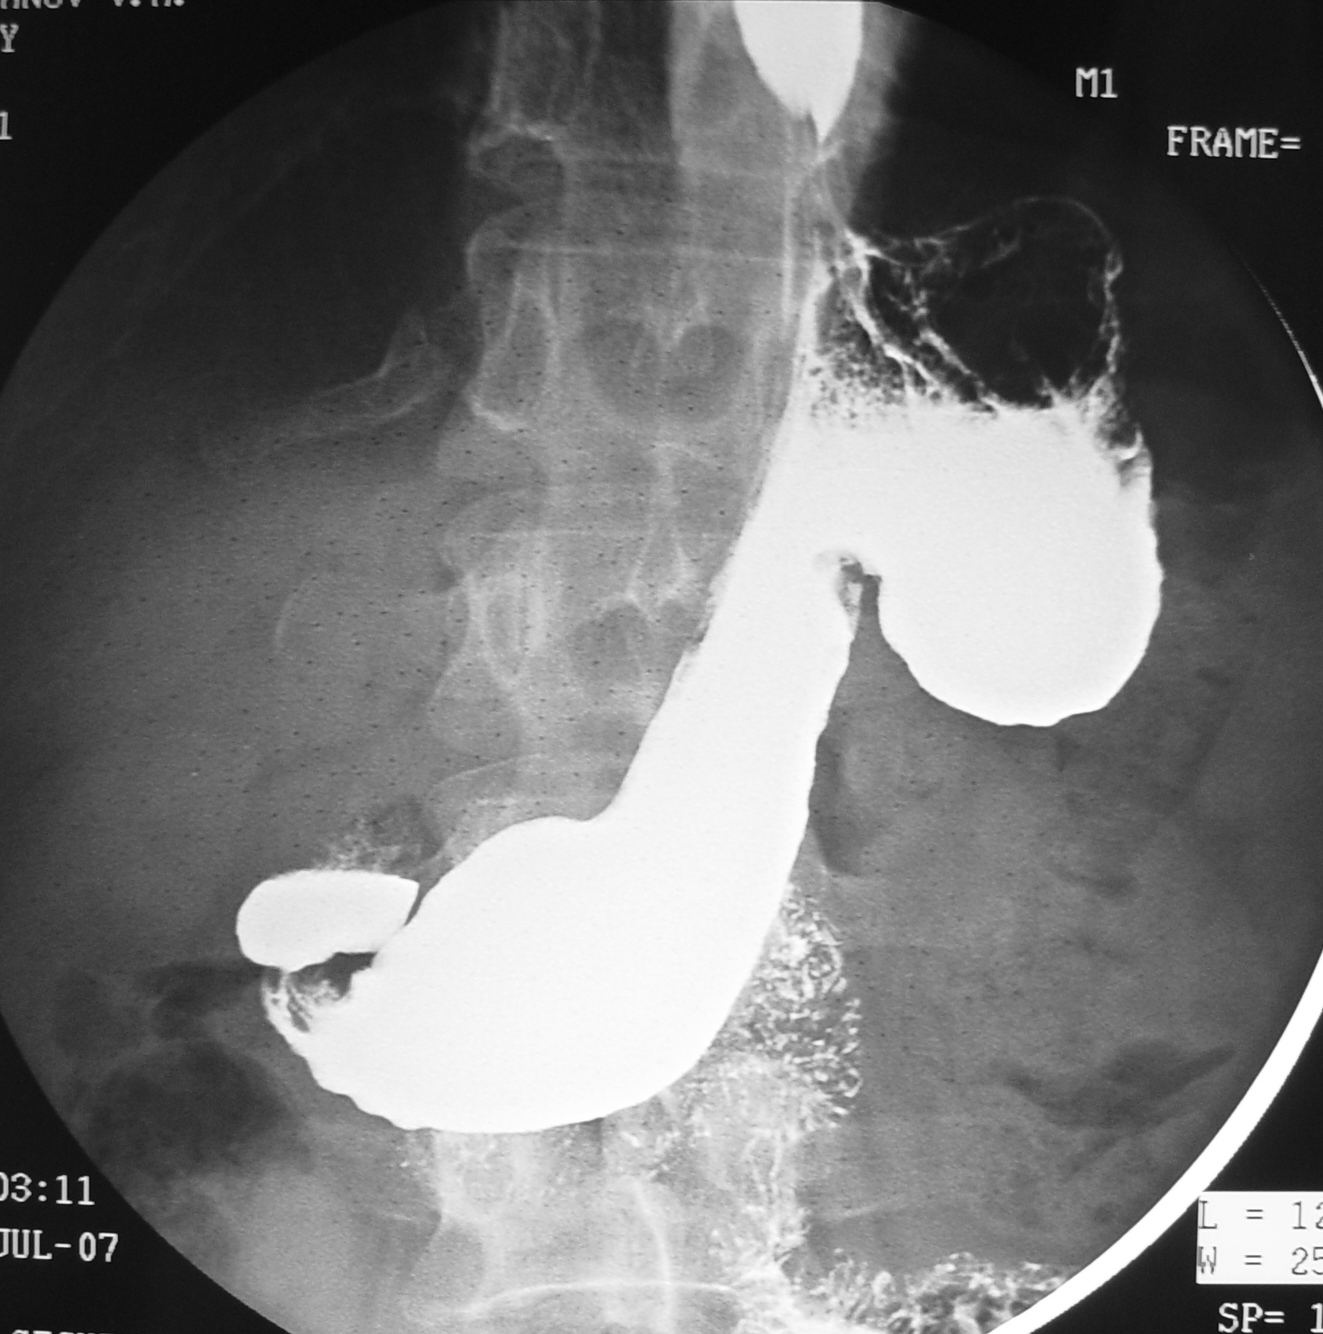

Но в представленном случае все было гораздо интереснее чем обычно, пациент прошел контрастное исследование пищевода и желудка. Жалоб небыло, родственники - врачи, просто профилактически обследовались. Вот что получилось:

Большое спасибо за участие в обсуждении.... итак на рентгенограммах желудка смутила деформация слизистой, это стало поводом для проведения КТ.

Что-то КТ-ушники молчат даже и Dr.Mario. На взгляд рентгенолога традиционной школы здесь в своде желудка выявлено, выступающее за его внешний контур экзофитное новообразование (показано стрелками). Если я не ошибся – хирурги его и нашли. Ещё мне показалось, что селезёнка великовата. Будет ли продолжение?

Итак, фактически на обзорной рентгенограмме желудка, мы имеем некоторое подобие варианта, так называемого "каскадоподобного желудка" с каскадообразной деформацией тела в проксимальном отделе, что может свидетельствовать, как о патологии, так и о норме.

Далее после тугого заполнения желудка и пальпации за экраном, желудок расправился, "каскад ушел", но по больной кливизне в области проксимальной трети тела желудка определяются гигантские складки слизистой, которые могут иметь место при локальной форме болезни Менетрие

На рентгенограммах, произведенных в боковой проекции указанные складки также четко дифференцируются.

Следовательно, диагноз - "локальная форма болезни Менетрие" или врожденные гигантские складки слизистой или ..... синонимов масса.

Валентин Львович, здесь нет признаков гипертрофии складок как при Менетрие. Это образование извне желудка и как бы сдавливает его стенку извне, и мне кажется оно подпаено к большой кривизне. КТ выполнено не очень грамотно с точки зрения подготовки и техники контрастирования.

Мне самому стало очень интересно; на КТ желудок растянут жидкостью, проллабирующих складок нет. Есть мягкотканное образование в левом под-диафрагмальном пространстве, которое как бы подпаено к желудку извне. Для карциноида-не та локализация, нет десмоидной реакции, нет характерного гипер-контрастирования (хотя КТ выполнена с нарушением общепринятой техники, не могу понять какие фазы и как делали, видимо пожалели контраста). Думать о карциноматозе-опять см. выше. Инородное тело? Нужен анамнез.